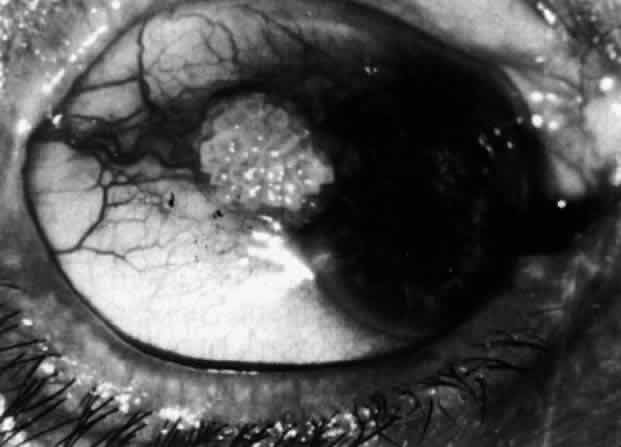

Fig. 30. Diffuse anterior scleritis. During the acute attack, the vessels are dilated

and distorted. New vessels or large vessels not normally seen have

appeared adjacent to the limbus. Fig. 30. Diffuse anterior scleritis. During the acute attack, the vessels are dilated

and distorted. New vessels or large vessels not normally seen have

appeared adjacent to the limbus.

|